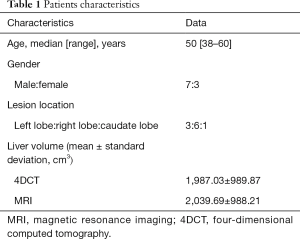

Comparison of GTVs before and after DR

GTVs obtained from 4DCT images were increased by an average of 4.23% (P<0.05) after DR, with GTVs following DR of each phase consistent with T2-weighted MRI image basic volume (Table 3, Figures 2,3). After DR all 4DCT image phases GTV were larger than DR before (except CT90, P<0.05).

Comparison of IGTVs before and after DR

The IGTV before DR was 383.89±342.53 cm3, with a 9.67% increase observed following DR (421.02±382.13 cm3), indicating that a significant increase in IGTV volume occurred after DR (P=0.018) (as shown in Table 4).

To assess the accuracy of image registration, we adopted three indicators: overlap degree of the liver, the displacement of the bifurcation point in the portal vein and celiac axis. Our results demonstrated that maximal displacement occurred in the cranial to caudal direction, in keeping with previously published reports (12,13). We used DR technology to analyze the application of 4DCT and MRI images in the delineation of the liver target. Our results revealed that the delineation of GTV size and range based on MRI is significantly greater than 4DCT images. GTV increased by an average of 4.23% (P<0.05) and IGTV volume increased by an average of 9.67% (P<0.05), suggesting that MRI may be a good supplement to CT image information. This not only improves the accuracy of HCC target identification using 4DCT but also may be beneficial in cases where there is a lot of exit noise on the original 4DCT image and failure to identify tumor boundaries.